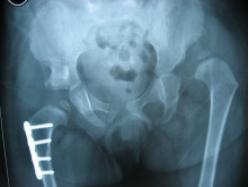

双侧髋关节脱位

右髋切开复位、Pemberton骨盆截骨 股骨近端短缩去旋转截骨术后

右侧术后8个月